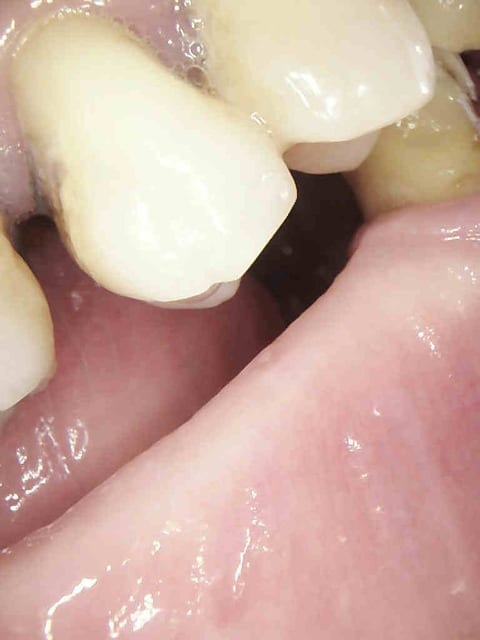

Tiens un cas s'approchant du tiens Chicot...comme je suis mauvais en Endo, j'essaye d'en faire le moins possible.

J'ai gardé vivant ce que je pouvais.

Le cas à 3 ans... RAS, j'ai vu la patiente il y a 2 mois.